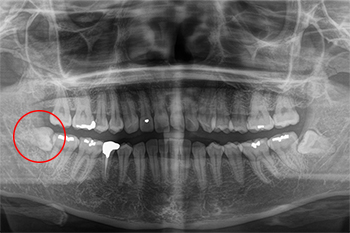

Case.01

| 主訴 | 右下の親知らずが出てきたので診て欲しい |

|---|---|

| 治療期間 | 約1週間 |

| 治療費用 | 4,400円 |

| 治療内容 | 右下の親知らずの抜歯。神経に近い可能性がある為、CTにて3Dでの撮影を行う。 |